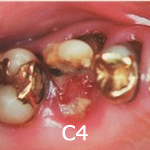

C4(歯根に達するむし歯)- 虫歯が大きくなりすぎて、歯が崩壊した状態です。神経は死んでしまっていることが多く、虫歯菌が血管から侵入し心臓病、腎臓病を引き起こす場合もありま す。治療が可能な場合は治療しますが、かぶせ物がしっかりできないほど虫歯が大きい場合、抜歯しないといけなくなってしまいます。